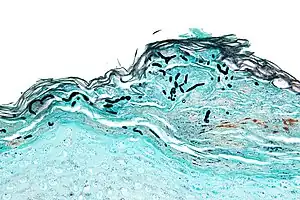

| Micrograph of a superficial dermatomycosis. The fungal organisms are the dark staining, thick, quasi-linear objects below with skin surface. Vulvar biopsy. GMS stain. | |

Examples of dermatomycosis are tinea and cutaneous candidiasis.These fungal infections impair superficial layers of the skin, hair and nails.